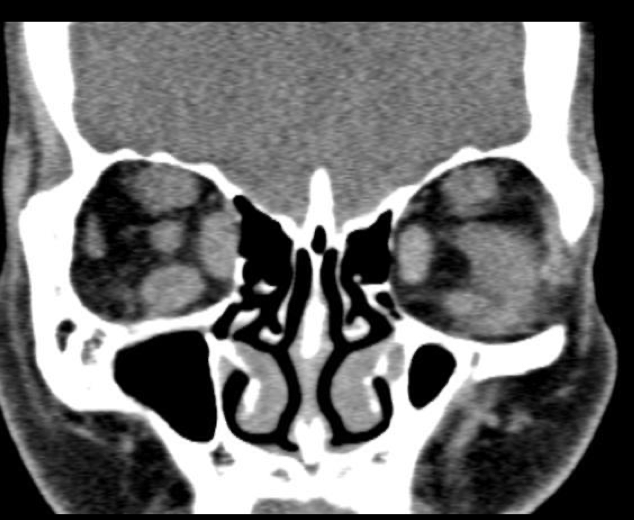

4

Q

Agrandamiento de los músculos extraoculares

Exoftalmos

Nervio óptico estirado

A

TC en Orbitopatia tiroidea